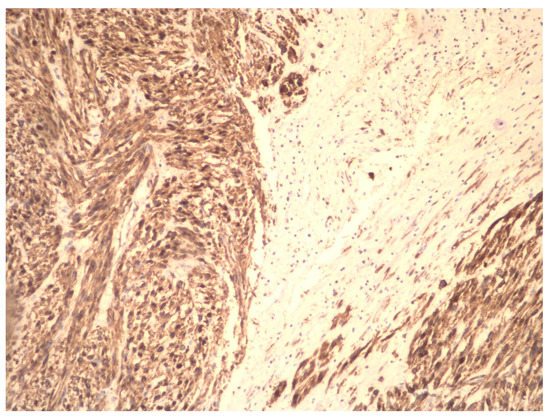

Molecular Insights in Uterine Leiomyosarcoma: A Systematic Review

3.2. Molecular Basis of Differentiation Uterine Leiomyosarcoma vs. Uterine Leiomyoma